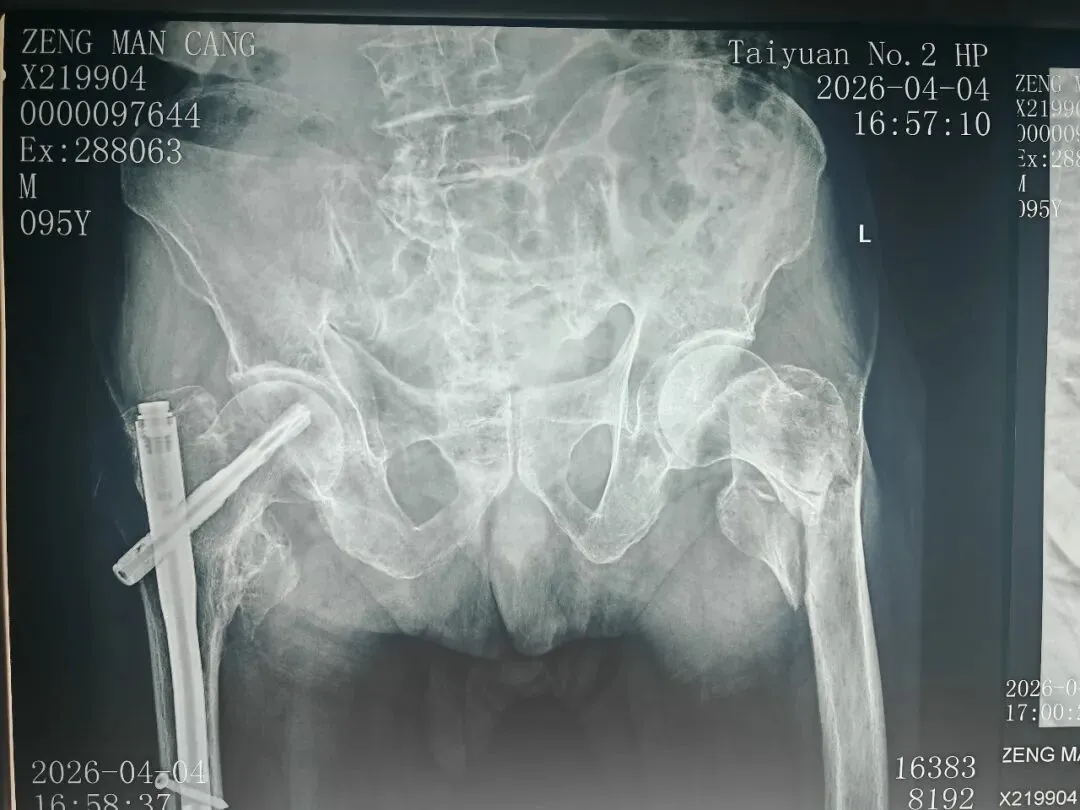

目前,患者确诊为"左股骨粗隆间粉碎骨折”,患者高龄,骨折粉碎性,分离移位明显,手术高难度,高风险。骨科团队考虑到患者年近百岁,身体机能退化,手术耐受性差,存在较高的手术风险。立即启动多学科协作诊疗模式,协调麻醉科,老年病科,检验科等相关科室专家进行紧急会诊,全面评估患者身体状况及手术风险。

术  前